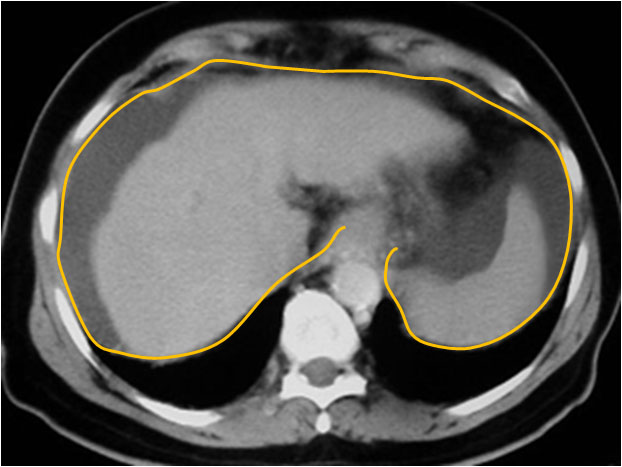

SIGNO DEL DIAFRAGMA

Cuando en la TC vemos líquido situado medial al diafragma (marcado en amarillo), es de localización intraperitoneal. Si se localiza por fuera, se trata de líquido pleural. Este signo no es válido cuando existe un derrame pleural en un hemitórax con un diafragma invertido, ya que entonces el derrame pleural se encuentra por dentro en vez de por fuera.